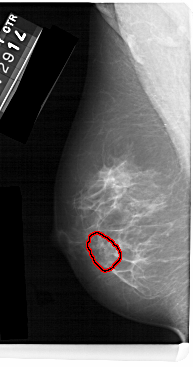

A_1477_1.LEFT_CC

FILE: A_1477_1.LEFT_CC.OVERLAY

TOTAL_ABNORMALITIES 1

ABNORMALITY 1

LESION_TYPE CALCIFICATION TYPE AMORPHOUS DISTRIBUTION CLUSTERED

ASSESSMENT 4

SUBTLETY 3

PATHOLOGY BENIGN

TOTAL_OUTLINES 1

BOUNDARY